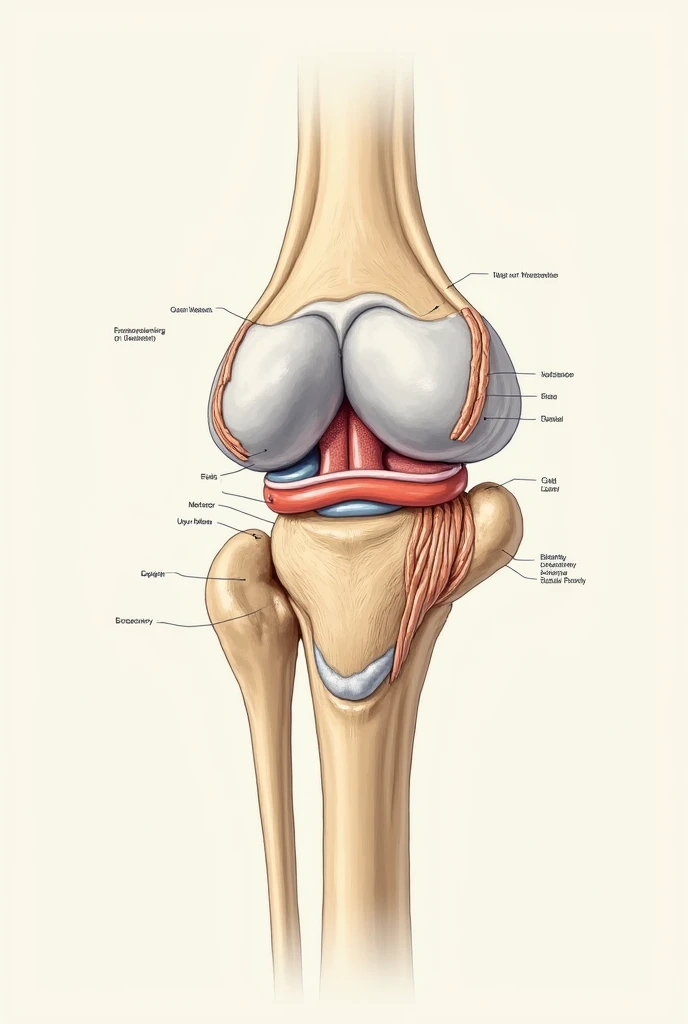

A close up of a white object with a human leg

Close-up of human knee,There is a bone in the middle, knee, Knees, surreal bone structure, Protruding bones, Realphotos, orthographic view, Look across the shoulder, medical depiction, Osteoarticular joints, computer generated, hyper realisitc, sharp bone structure, joint, digital painted

medical depiction

Osteoarticular joints